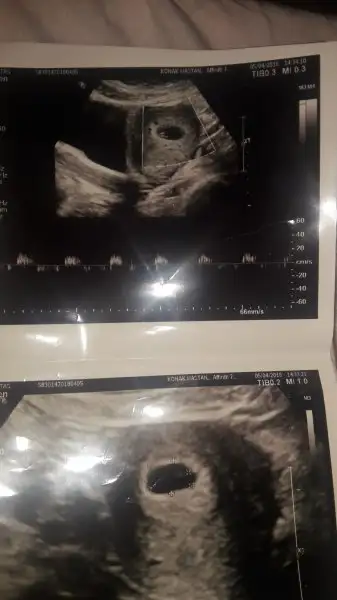

Selam kizlar bende kasimda dogum yapicam çatlatma ignesiyle 16.gun idrar testinde pozitifi gördüm 17.gunde bhcg 292 ćikti iki gun sonra tekrarladim 1243 çıktı iki gun sonrda dr gittim keseyi gördum zaten keseyi gordukten 10 gun sonrq yani dun gittim tam 6 haftaliktı kalp atislarini Duydum ve nokta gibi icinde bebek kipirtisi vardi yani bende hamileyim bende kasim annesi olucam kizlar sayfanizi gunlerdir okuyorum en basindan beri okudum nerdeysw bugunde yazim dedim bakın benisin ilk resmide buüstteki kesenin kösesinde nokta gibi bebiş sizde atsaniza kizlar bebeklerinizin resmini